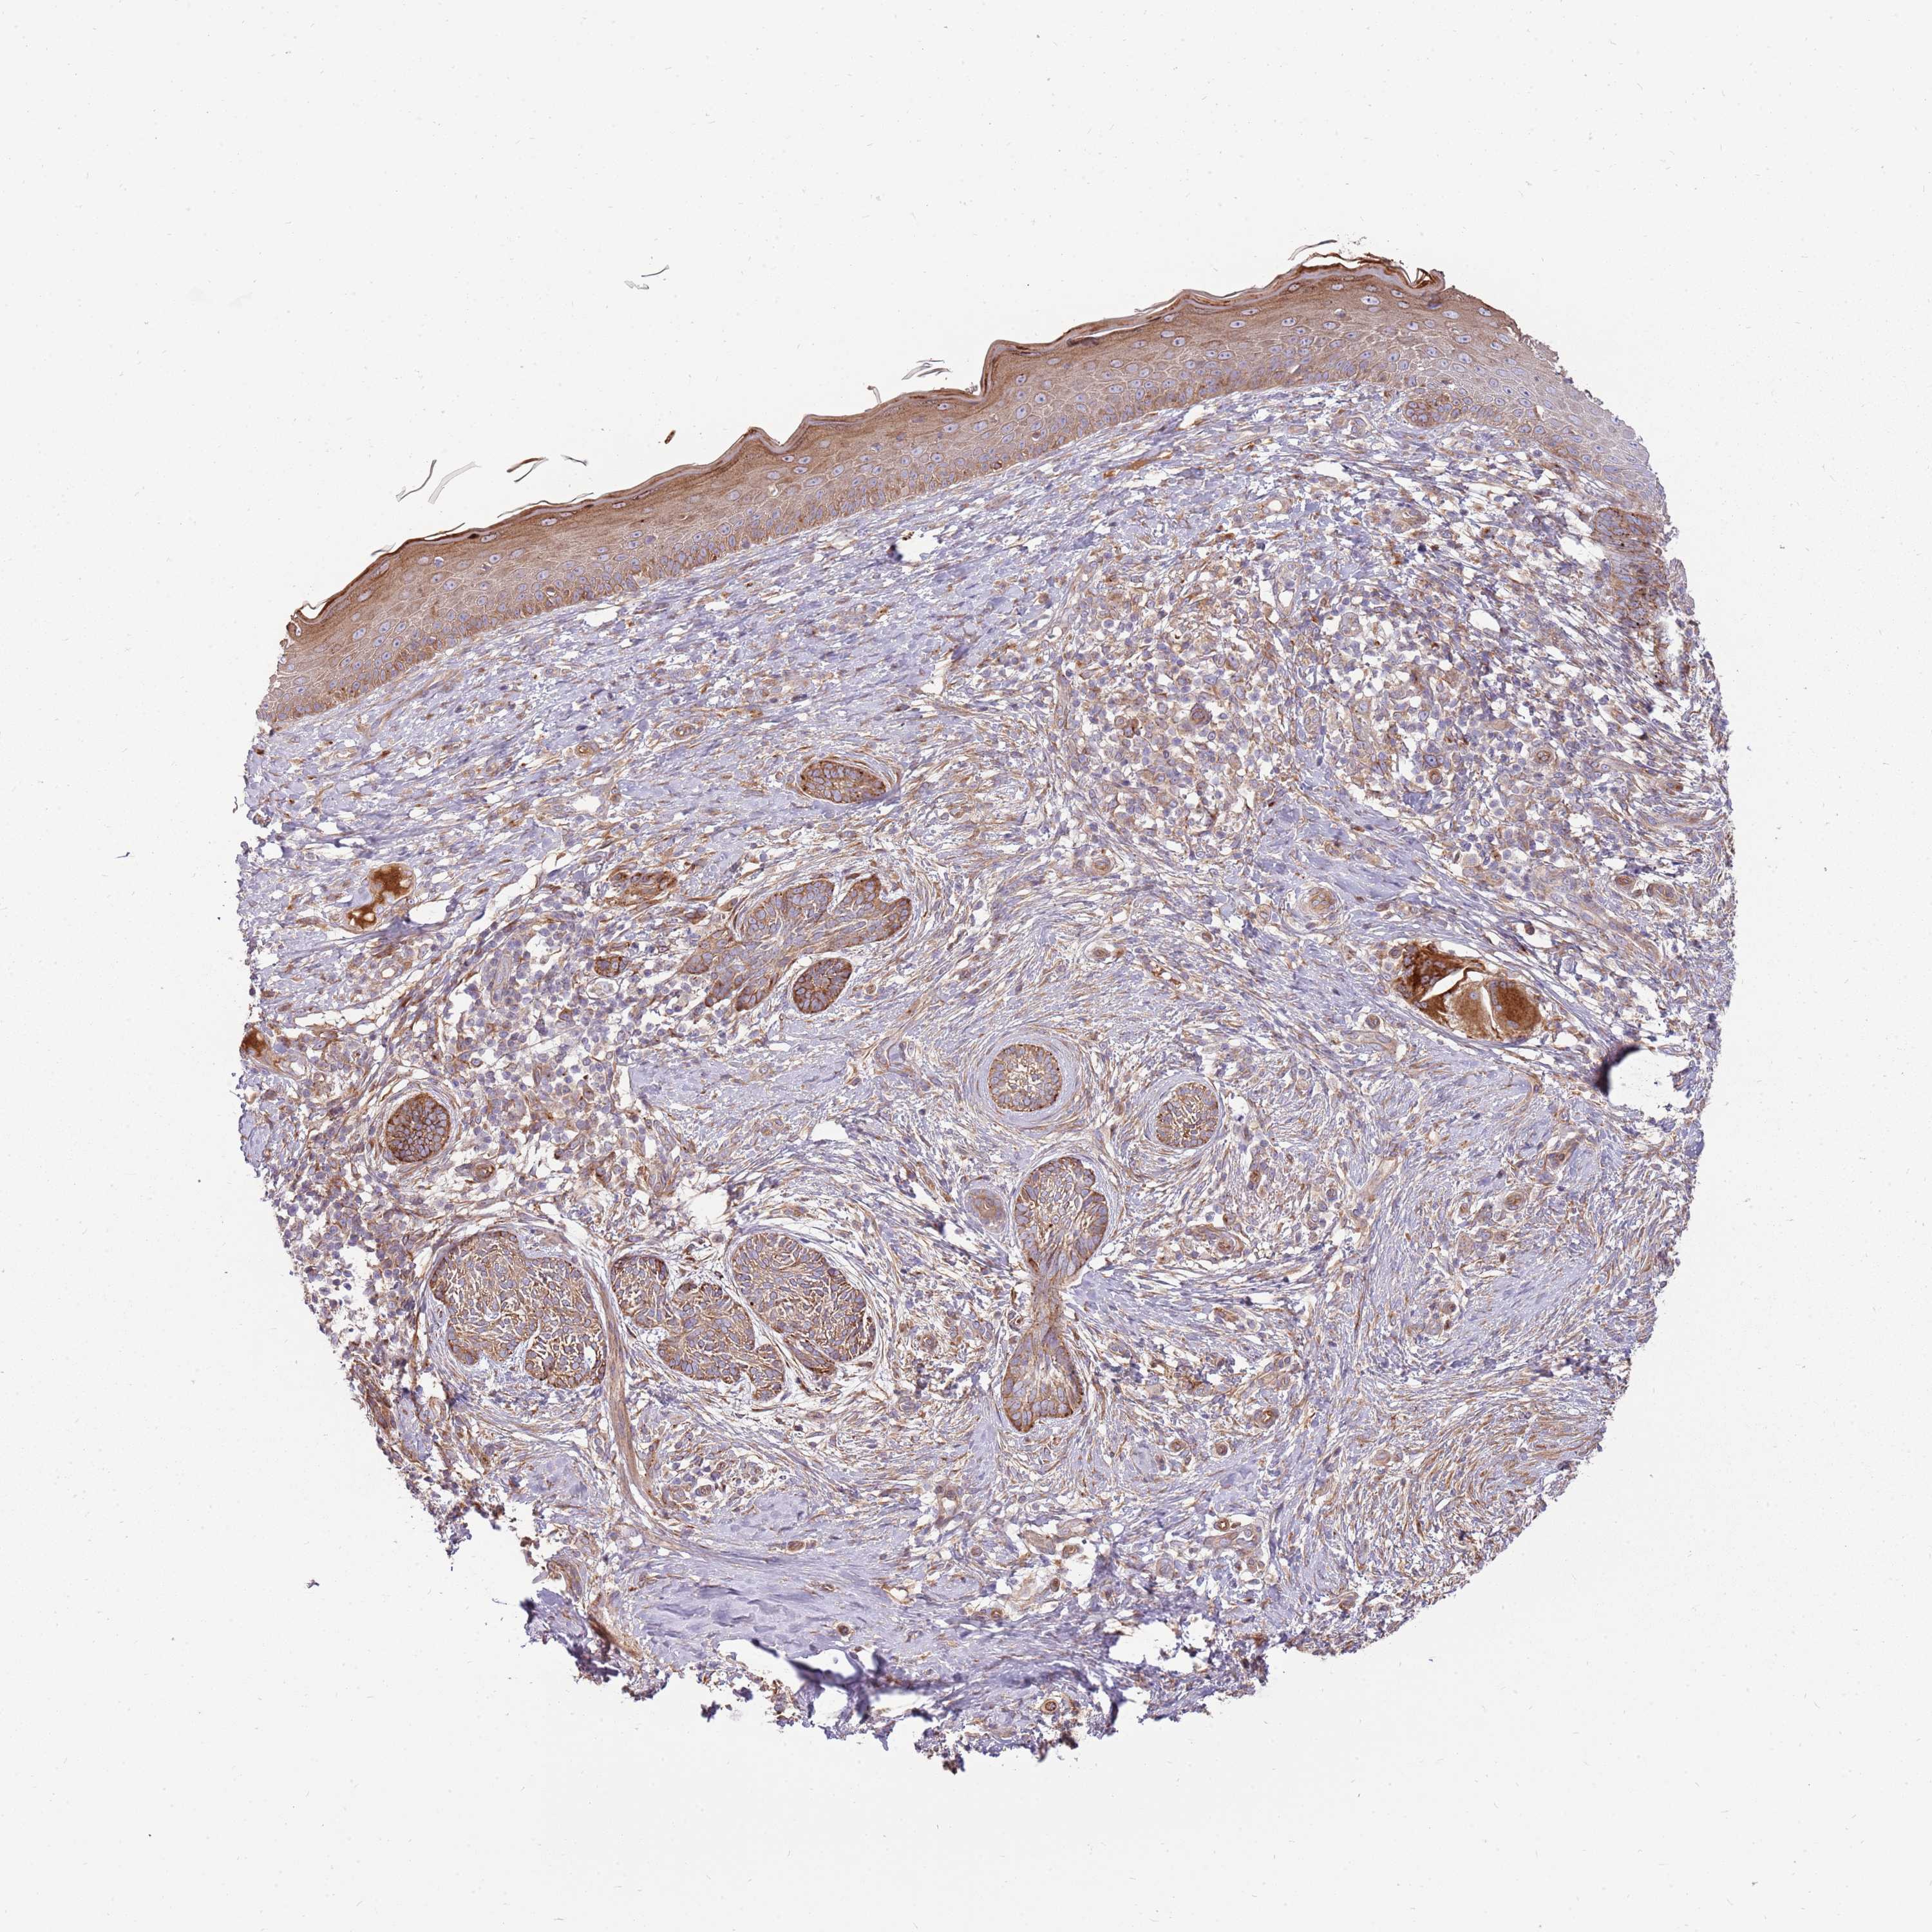

Basal cell and squamous cell cancer

SKIN CANCER - Protein expressioni

A mouse-over function shows sample information and annotation data. Click on an image to view it in a full screen mode. Samples can be filtered based on level of antibody staining by selecting one or several of the following categories: high, medium, low and not detected. The assay and annotation is described here.

Each image is clickable and will lead to virtual microscopy that enables deeper exploration of all samples and also displays staining intensity scores, fraction scores and subcellular localization as well as patient and tissue information for each sample.

Antibody HPA048904

Staining

Medium

Intensity

Moderate

Quantity

75%-25%

Location

Cytoplasmic/membranous,nuclear

Squamous cell carcinoma, NOS